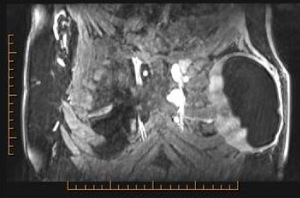

She went on to have a MRI scan to exclude device rupture which showed an enhancing periprosthetic fluid collection surrounding an intact implant. There was abnormal enhancement of the lymph nodes in the left second and third intercostal space and an enlarged node in the fourth intercostal space (Figure 2). An ultrasound guided fine needle aspirate (FNA) of the left pericapsular fluid and internal mammary node was then completed. The pericapsular fluid showed no sign of malignancy with a population of small to medium lymphocytes. The flow cytometry for this specimen showed a normal lymphoid population and surface molecule expression. The left internal mammary node FNA was non-diagnostic, and due to the location of the node, core biopsy was deemed unfeasible.